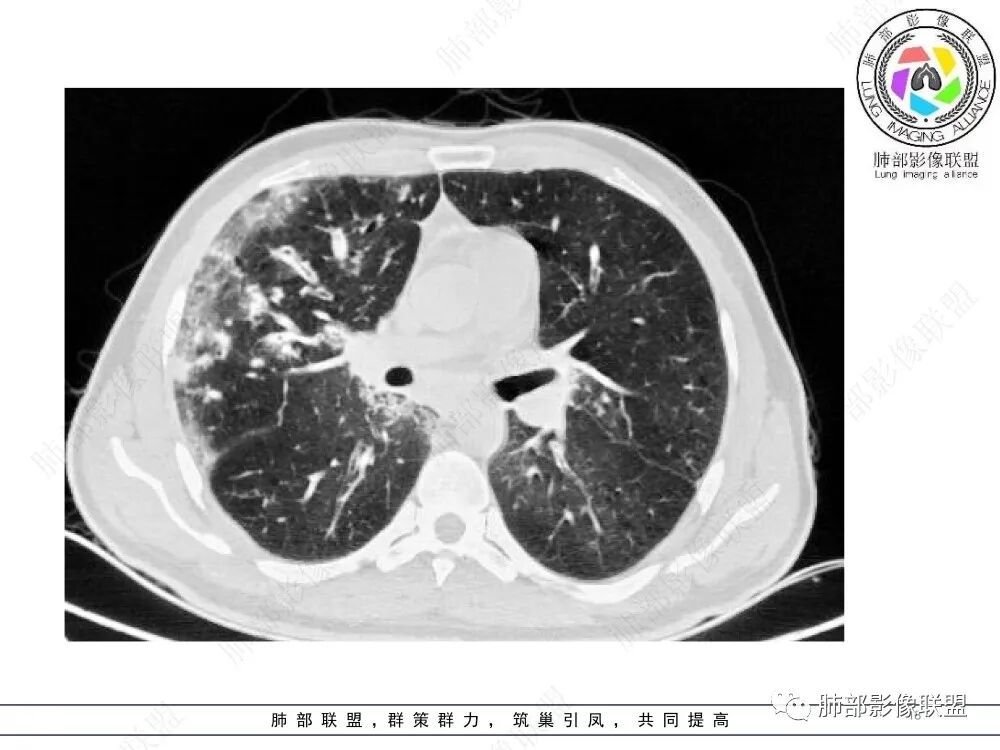

两肺多发弥漫性腺泡结节,支气管壁增厚,抗炎治疗后病变范围较前进展,沿支气管血管束分布,两肺见多发树芽及增厚扩张支气管,以右中叶及左上叶舌段为著,年轻患者,慢性病史,扩张支气管周围肺野未见肉芽肿性病变,抗炎治疗无效可排除诺卡及铜绿感染,综合分析首选NTM,其次气道侵袭性曲霉。

两肺支气管壁增厚,散在斑片状及树芽状影,抗炎治疗后病变范围进展,沿支气管血管束分布,两肺多发结节、树芽、实变及囊腔影,年轻患者,慢性病史,肺气肿背景,考虑气道侵袭性曲霉,鉴别NTM+铜绿。

晨读:最关键的有三点:1、临床表现及病史:35岁,男性,慢性刺激性咳嗽2月,吸烟史17年,没有糖尿病和其他免疫缺陷病史。这儿应该隐瞒了关键的吸入环节,存在大量曲霉孢子的工作环境没给。2、第一次影像改变:广泛的支扩,支气管壁增厚,多发的树芽,部分区域已经伴有支气管周围的渗出,少量实变。3、20多天后复查的影像,原有支扩,支气管壁增厚基础上的大量渗出,实变,伴结节,胸膜下累及。

上述表现最符合的就是气道侵袭性曲霉菌病(IPA),刺激性咳嗽2月支持最初的气道改变:广泛的支扩,支气管壁增厚(支气管粘膜充血,水肿,以及伪膜形成)树芽征,而后期大量支气管周围渗出,实变,伴结节,胸膜下累及,也符合IPA的进展表现,病史中未提及是否有胸闷,气喘等(估计后期有,没提供而已)。

2.胸部CT:两肺广泛的支扩,支气管壁增厚,多发的树芽影,部分伴有支气管周围的渗出,少量实变。不足一月复查,原有支扩、支气管壁增厚基础上伴有大量渗出,实变,结节,胸膜下累及。

3.综合分析:首先病灶沿支气管分布,呈树芽征及实变影,相应支气管壁广泛增厚,其次病变范围比较广泛,几乎累及所有叶段,这种表现常高度提示气道播散,经过对症抗感染治疗20多天后,胸部CT影像明显进展。符合IPA的进展表现。